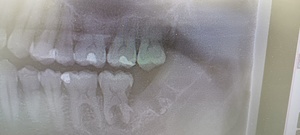

少し見えて横になった親知らず

親知らずのレントゲン

親知らずの歯はどこの場所?

親知らずは、永久歯(大人の歯)の中で最後に発育する歯で、中切歯(最前方の前歯)から数えて8番目の最後方歯に位置しています。

18歳前後から生えてくるので、20代前半までに抜歯するのがおすすめです。

親知らずは必ずしも抜かなければいけないものではありませんが、痛みや腫れを繰り返す場合や、他の歯に影響を及ぼしてしまう可能性がある場合は抜歯を行う必要があります。

親知らずが腫れる理由は?

親知らずの半分が歯ぐきの中に埋まっていたり、傾いていたりするので、親知らずの周りの歯ぐきの“くぼみ”に歯垢(プラーク、細菌)が溜まりやすく不潔となり、体調を崩し免疫力が落ちると、そこから炎症を起こし、周辺の歯ぐきが腫れてきます。

親知らずを原因とする歯周炎は「智歯周囲炎」と呼ばれ、通常のむし歯による歯周炎に比べ、炎症の程度が強いのが特徴です。このため、痛みがひどく、頬まで腫れた、口が開きにくいといった重い症状を引き起こしやすくなります。